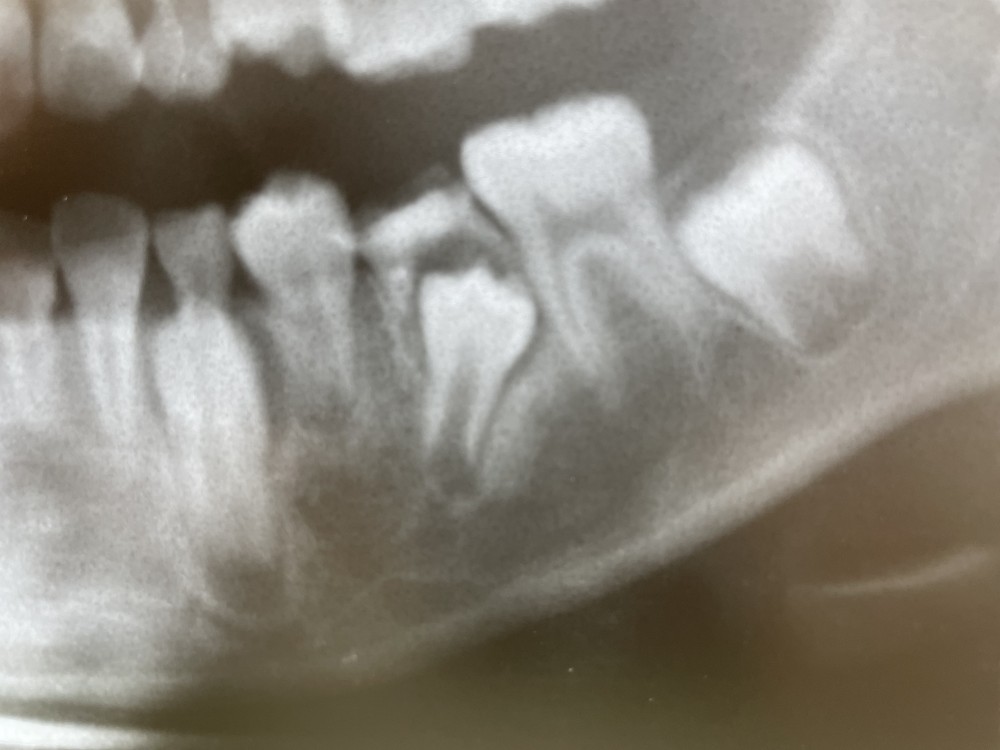

下のエックス線写真は、9才10ヶ月のものです。

左下Eは、口腔内では、レジン修復済みに見えるのですが、

エックス線写真では、すでに左下5の萌出を妨げていることが確認できます。